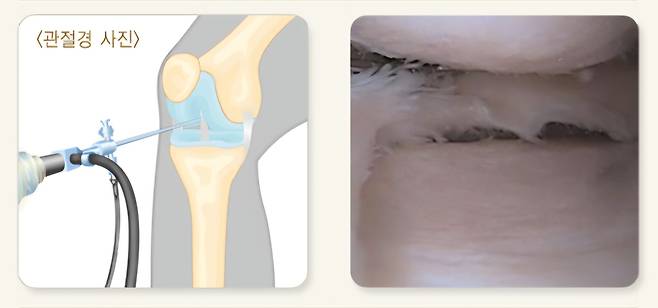

연구진은 치료 해법을 찾기 위해 필요에 따라 다양한 조직으로 분화할 수 있는 유도만능줄기세포에 주목했다. 이 줄기세포를 연골세포로 분화시킨 뒤 아주 작은 공 형태의 3차원 조직으로 만들어 관절 안에 주사로 집어넣는 ‘MIUChon’ 치료제를 개발했다. 흔히 ‘연골 스페로이드’라 불리는 이 세포치료제는 이전까지의 단순한 세포 주입 방식과 달리, 연골 조직의 구조를 유지한 상태로 손상된 연골에 전달되도록 만들어졌다.

치료제의 효과 검증을 위해 쥐와 토끼를 비롯해 사람의 관절 구조와 유사한 개(비글)와 미니피그 같은 실험동물을 대상으로 실험을 진행했다. 그 결과, 손상된 연골 부위의 두께와 부피가 증가하고, 연골이 닳아 생긴 결손 부위가 실제로 회복되는 양상이 확인됐다. 보행 분석에서도 관절 기능이 개선된 것으로 나타났다.

특히 영상 검사와 조직 분석에선 주입된 인간 유래 연골세포가 관절 내 손상 부위에 실제로 정착해 새로운 연골 기질을 만들어내는 과정이 관찰됐다. 작용 기전은 크게 두 가지 방식으로 나타났다. 먼저 주입된 연골 스페로이드가 손상 부위에 직접 붙어 새로운 연골 조직을 형성하는 직접 재생 작용이 일어났다. 이와 함께 연골세포가 성장인자와 항염증 신호 물질을 분비해 관절 안의 염증을 줄이고 연골이 다시 만들어지기 좋은 환경을 조성하는 간접 작용도 나타났다. 연구진은 이에 대해 세포치료제가 일시적인 효과를 내는 데 그치지 않고 연골 재생에 직접적으로 관여할 수 있음을 보여주는 것이라고 설명했다.